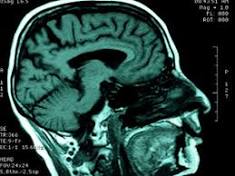

Chemo May Prolong Lives of Some With Brain Cancer In the United States, nearly 23,000 adults were diagnosed with brain cancer in 2015, according to the U.S. National Cancer Institute (NCI). There are ...